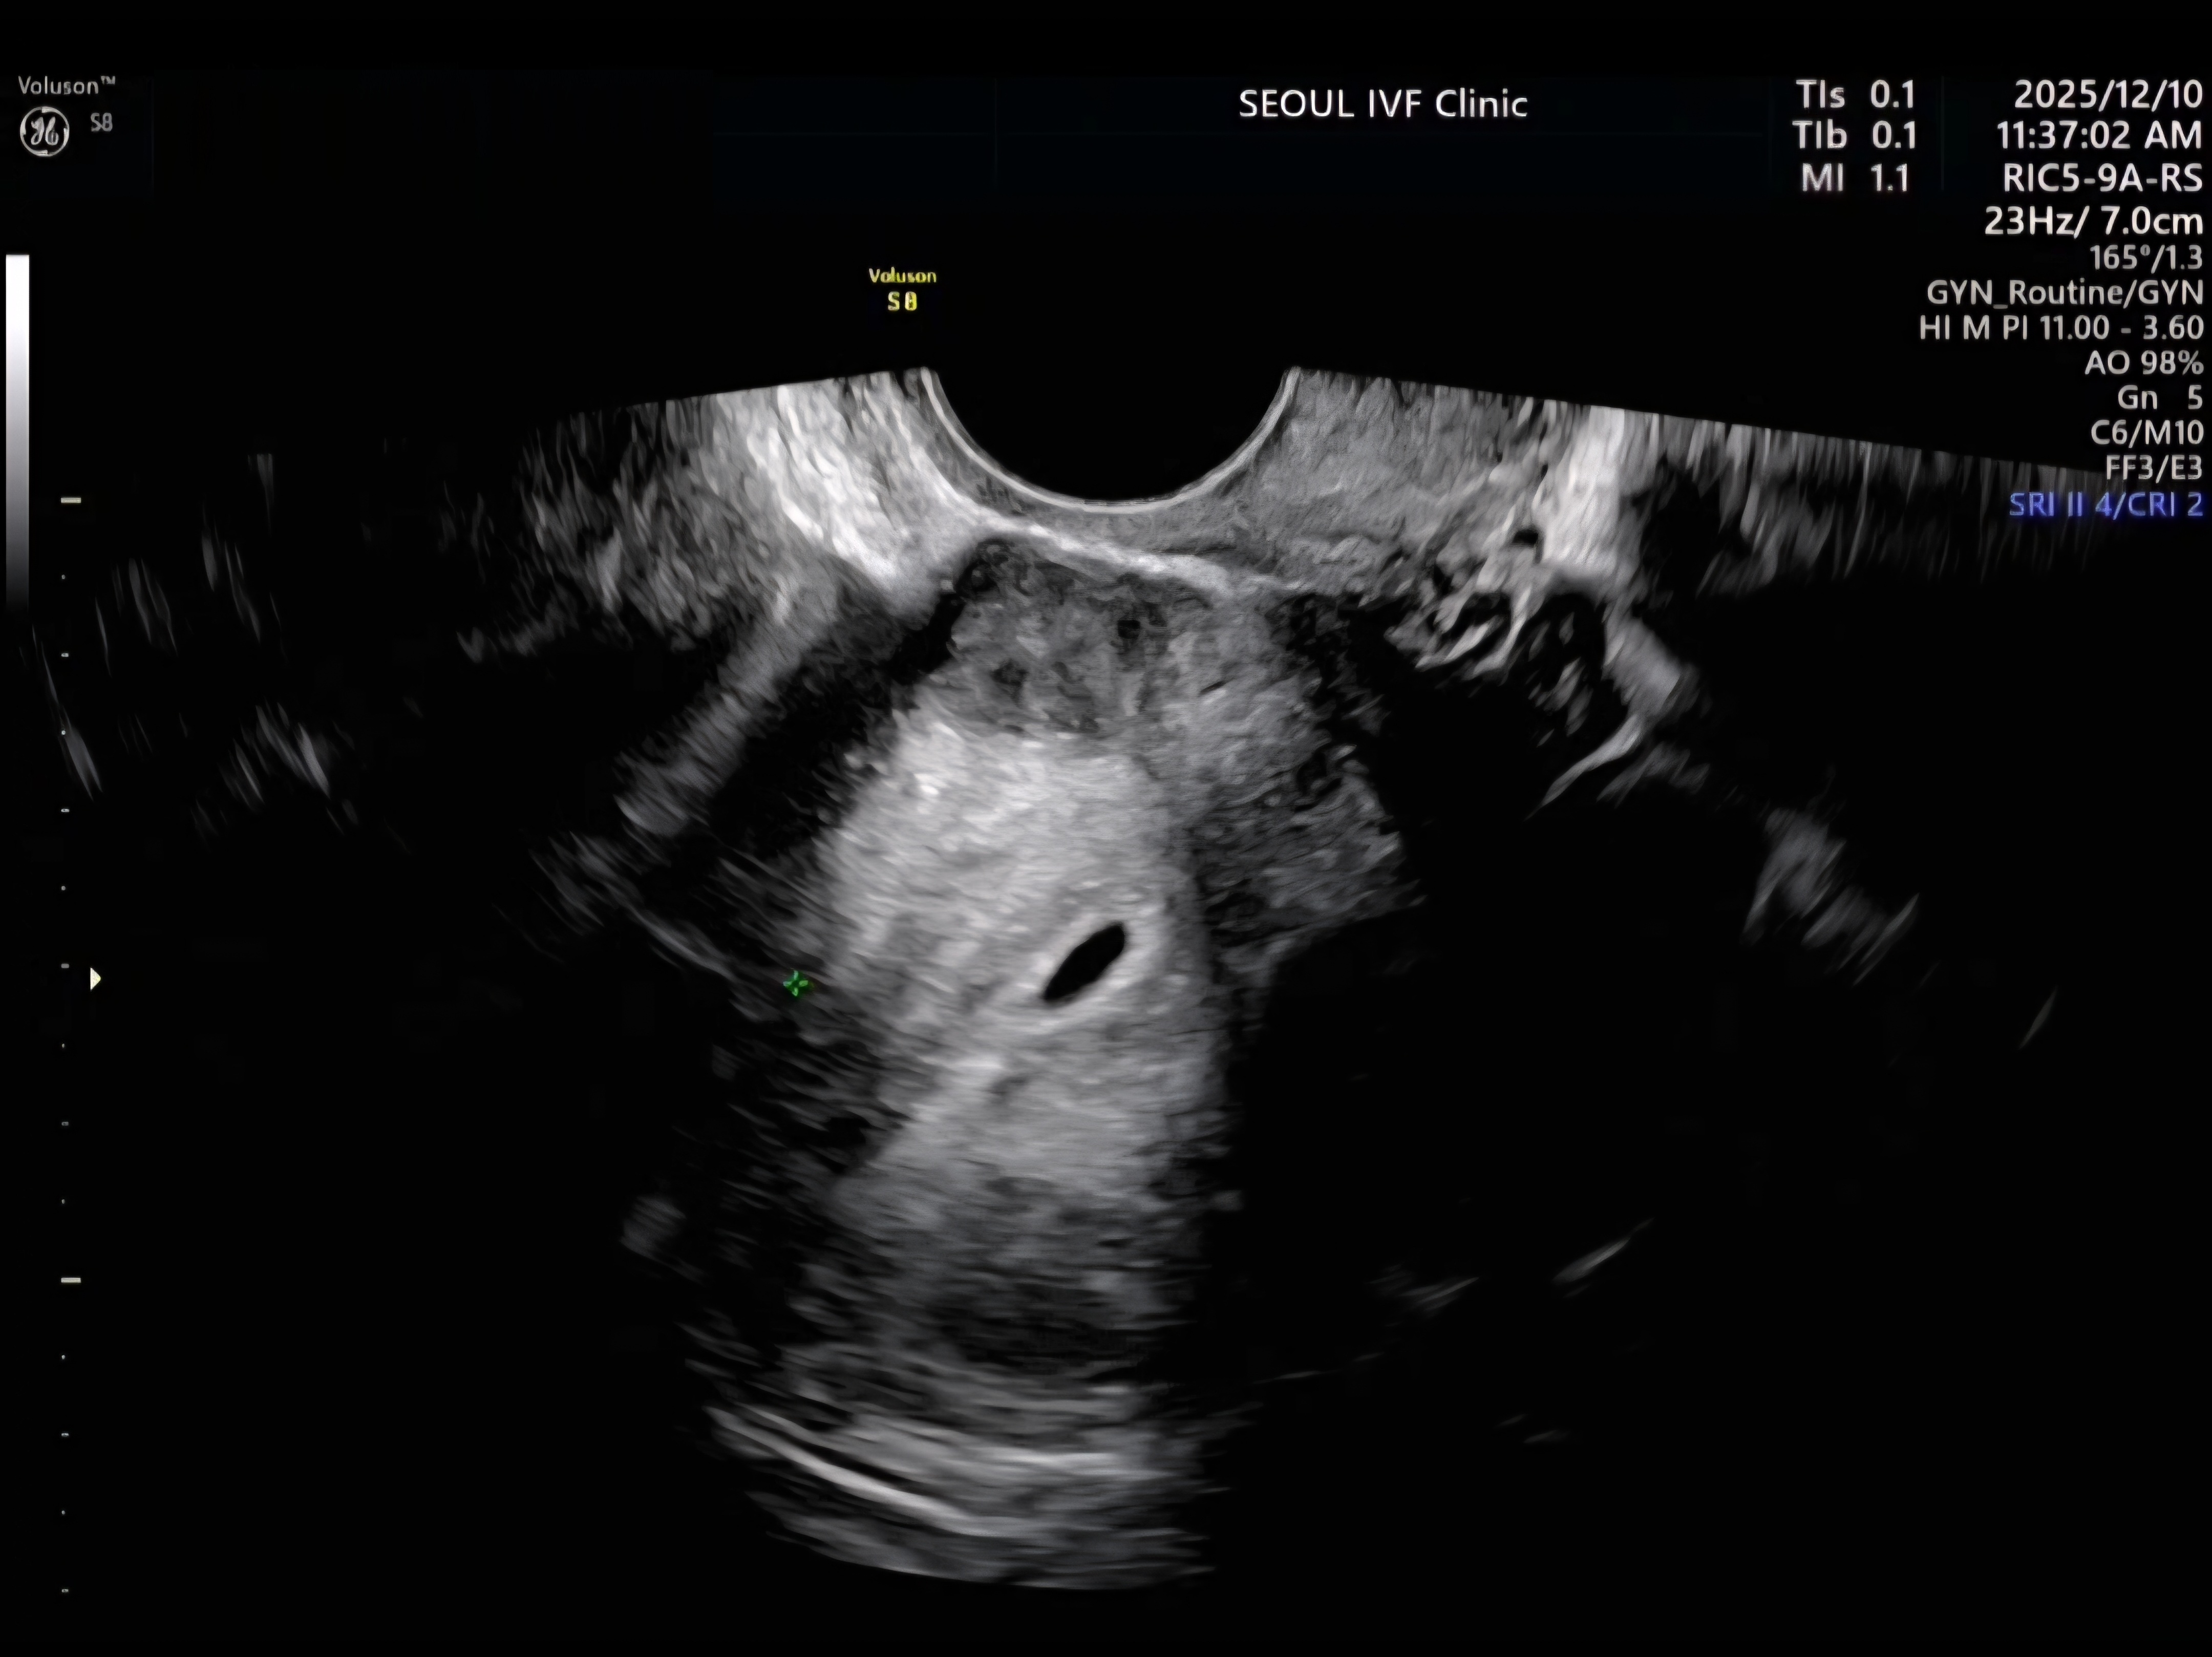

| 가슴 떨리는 임신 이야기를 공유해 주세요. | 첫 시도에 임신이 되는 건 로또라고들 하는데, 큰 어려움 없이 바로 임신이 되어 정말 다행이라는 생각이 들었습니다. 임신 테스트기에서 두 줄을 보았던 그 순간은 지금도 잊을 수 없는 기억으로 남아 있습니다. |

| 서울IVF여성의원의 난임 치료에 대해 말씀해 주실 것이 있나요? | 이경훈 원장님께서 친절하고 꼼꼼하게 신경 써 주셨고, 간호사 분들께서도 하나하나 자세히 설명해 주시며 공감해 주셔서 치료 과정이 훨씬 편안하게 느껴졌습니다. 의료진 모두에게 진심으로 감사한 마음입니다. |